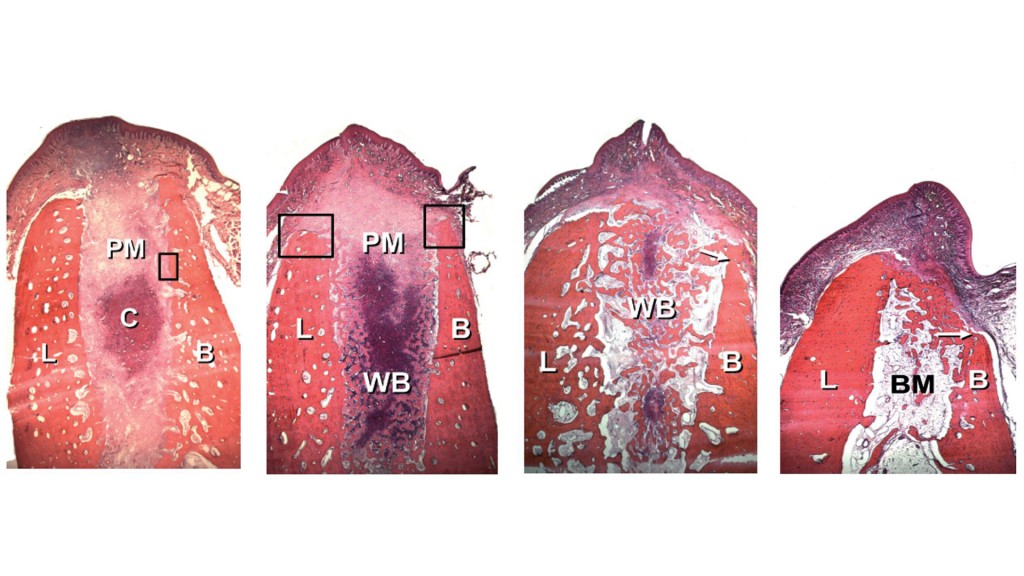

Anche se non siamo anatomopatologi credo che entrambi possiamo comprendere le immagini qua sopra. La prima si riferisce ad un alveolo di cane una settima dopo l’estrazione, l’ultima ad un alveolo di cane otto settimane dopo l’estrazione. Questo esperimento dimostra che il processo alveolare SI RIASSORBE, per lo più in orizzontale (ma anche in verticale), e per lo più a carico dell’aspetto vestibolare.

Anche se non siamo anatomopatologi credo che entrambi possiamo comprendere le immagini qua sopra. La prima si riferisce ad un alveolo di cane una settima dopo l’estrazione, l’ultima ad un alveolo di cane otto settimane dopo l’estrazione. Questo esperimento dimostra che il processo alveolare SI RIASSORBE, per lo più in orizzontale (ma anche in verticale), e per lo più a carico dell’aspetto vestibolare.

Guarda cosa ha dimostrato Botticelli nel 2006:

Le prime due immagini ti mostrano cosa a avviene a due mesi se metti un impianto in un “buco” artificiale fatto in osso guarito e in un alveolo post estrattivo; le ultime due ti mostrano la stessa cosa a quattro mesi. Come puoi vedere l’osso alveolare dopo l’estrazione si riassorbe esattamente come se non ci fosse l’impianto mentre nel caso del “buco” artificiale anche se viene scollato un lembo il riassorbimento è irrilevante!